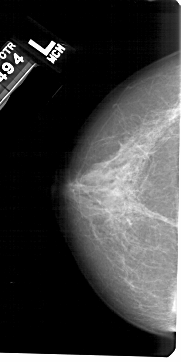

A_1520_1.LEFT_CC

LEFT_CC LINES 5416 PIXELS_PER_LINE 2701 BITS_PER_PIXEL 12 RESOLUTION 43.5 NON_OVERLAY